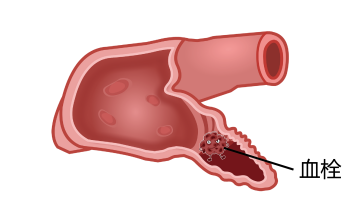

心房颤动患者容易发生脑卒中,是因为心房不能规律地收缩,血液容易在心房内瘀滞而形成血栓,这种血栓往往比较大,随着心脏的搏动,血栓会从左心耳中跑出来。这种血栓可以跑到肢体动脉引发栓塞,严重者需要截肢,也可以跑到大脑里会导致卒中,轻则偏瘫致残,重则痴呆、植物人、死亡。目前认为非瓣膜性心房颤动患者的血栓90% 来自左心耳(图2)。

图2.心脏结构、心耳血栓及脑栓塞